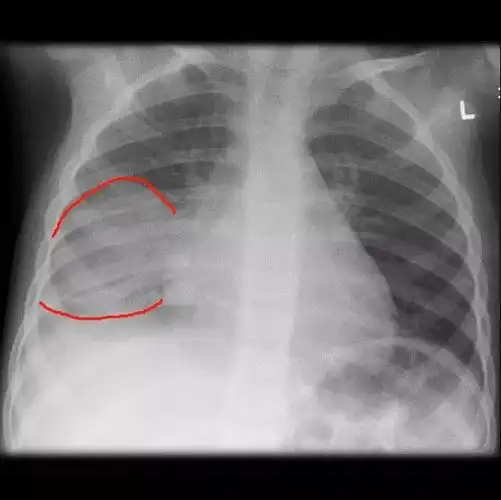

小孩得了肺炎,我们在日常中该如何护理呢? 正常胸片

胸片可见两肺弥漫炎性渗出影,因此诊断为小儿支气管肺炎

儿童肺炎时胸片怎么看呢